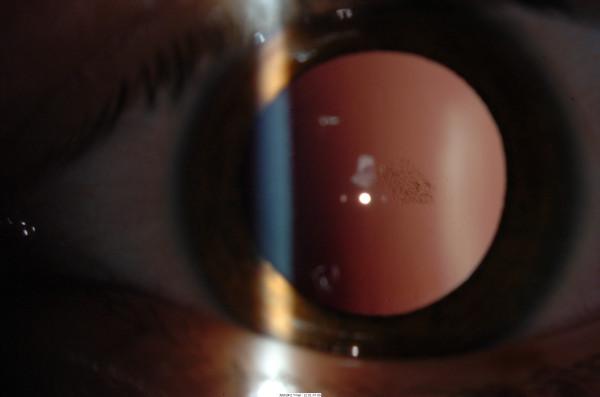

We describe two children with atopic dermatitis, treated with cutaneous corticosteroids, both of whom were diagnosed with bilateral posterior sub-capsular cataracts.

我们描述了两名患有特应性皮炎并接受皮肤皮质类固醇治疗的儿童,他们均被诊断为双侧后囊下白内障。